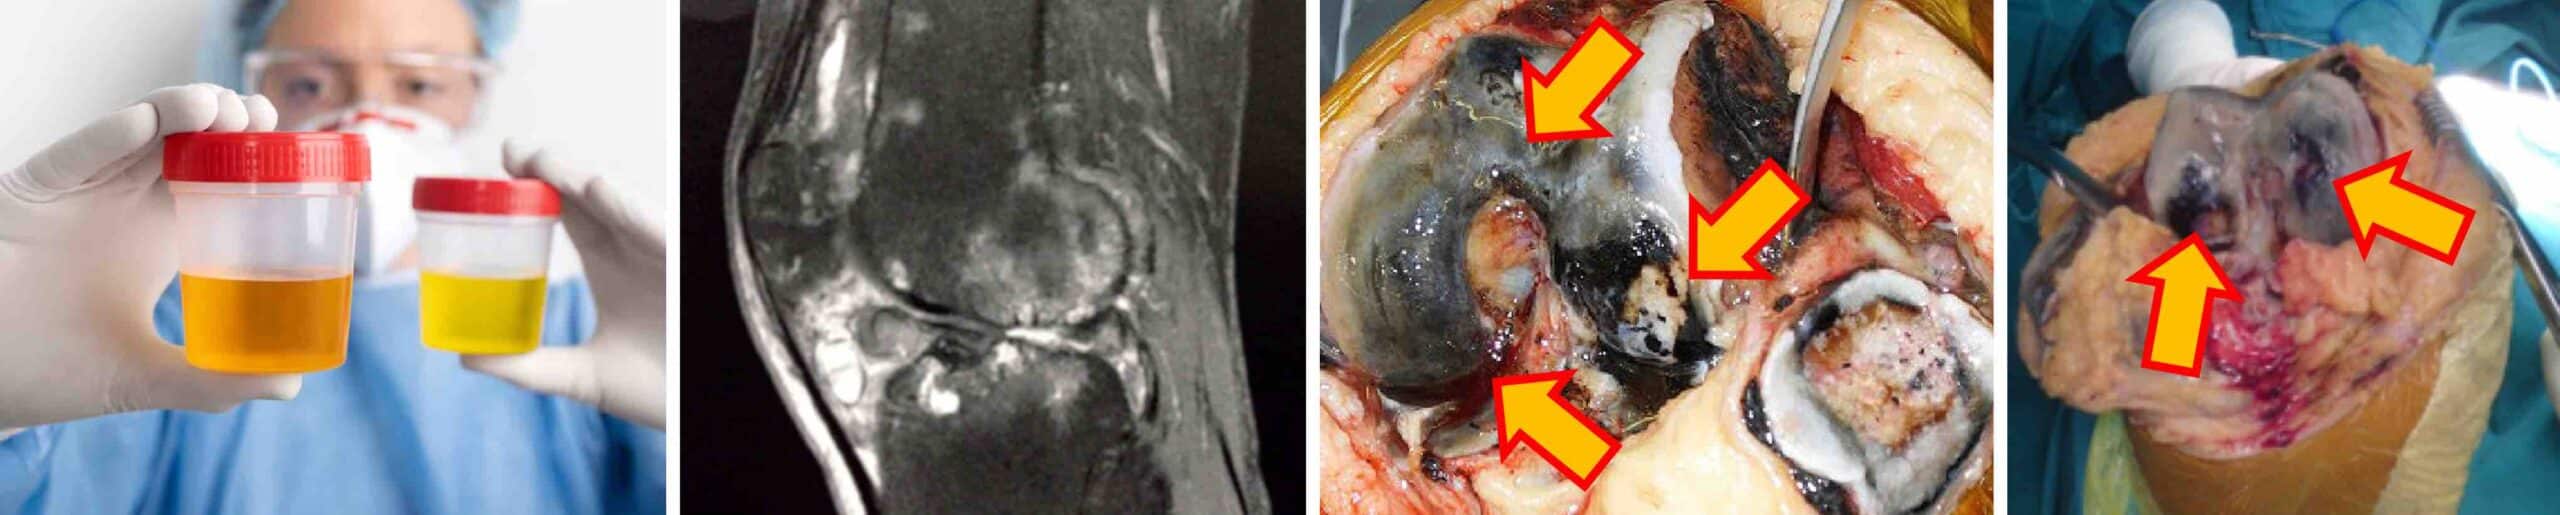

Os sintomas da ocronose no joelho costumam se manifestar a partir dos 30 a 40 anos de idade. Os principais sintomas da ocronose no joelho são: dor crônica que piora com o passar do tempo, rigidez articular após o joelho ficar algum tempo imóvel, estalos, crepitações, diminuição da amplitude de movimentos, inchaço e incapacidade funcional significativa nas fases mais avançadas. Durante procedimentos cirúrgicos, o cirurgião identifica que a cartilagem do joelho com ocronose tem uma coloração escurecida ou azulada, que é característica da ocronose.

O diagnóstico da ocronose no joelho é feito pela história clínica completa, exame físico do joelho doente e exames complementares de imagem e laboratório. Na história clínica o paciente conta que sua urina é escurecida. No exame de urina a dosagem de ácido homogentísico está elevada. No RX e na ressonância magnética do joelho notam-se sinais de artrose precoce. Na artroscopia é possível identificar a cartilagem do joelho escurecida. Uma biópsia dos tecidos afetados confirma a presença do pigmento ocronótico.